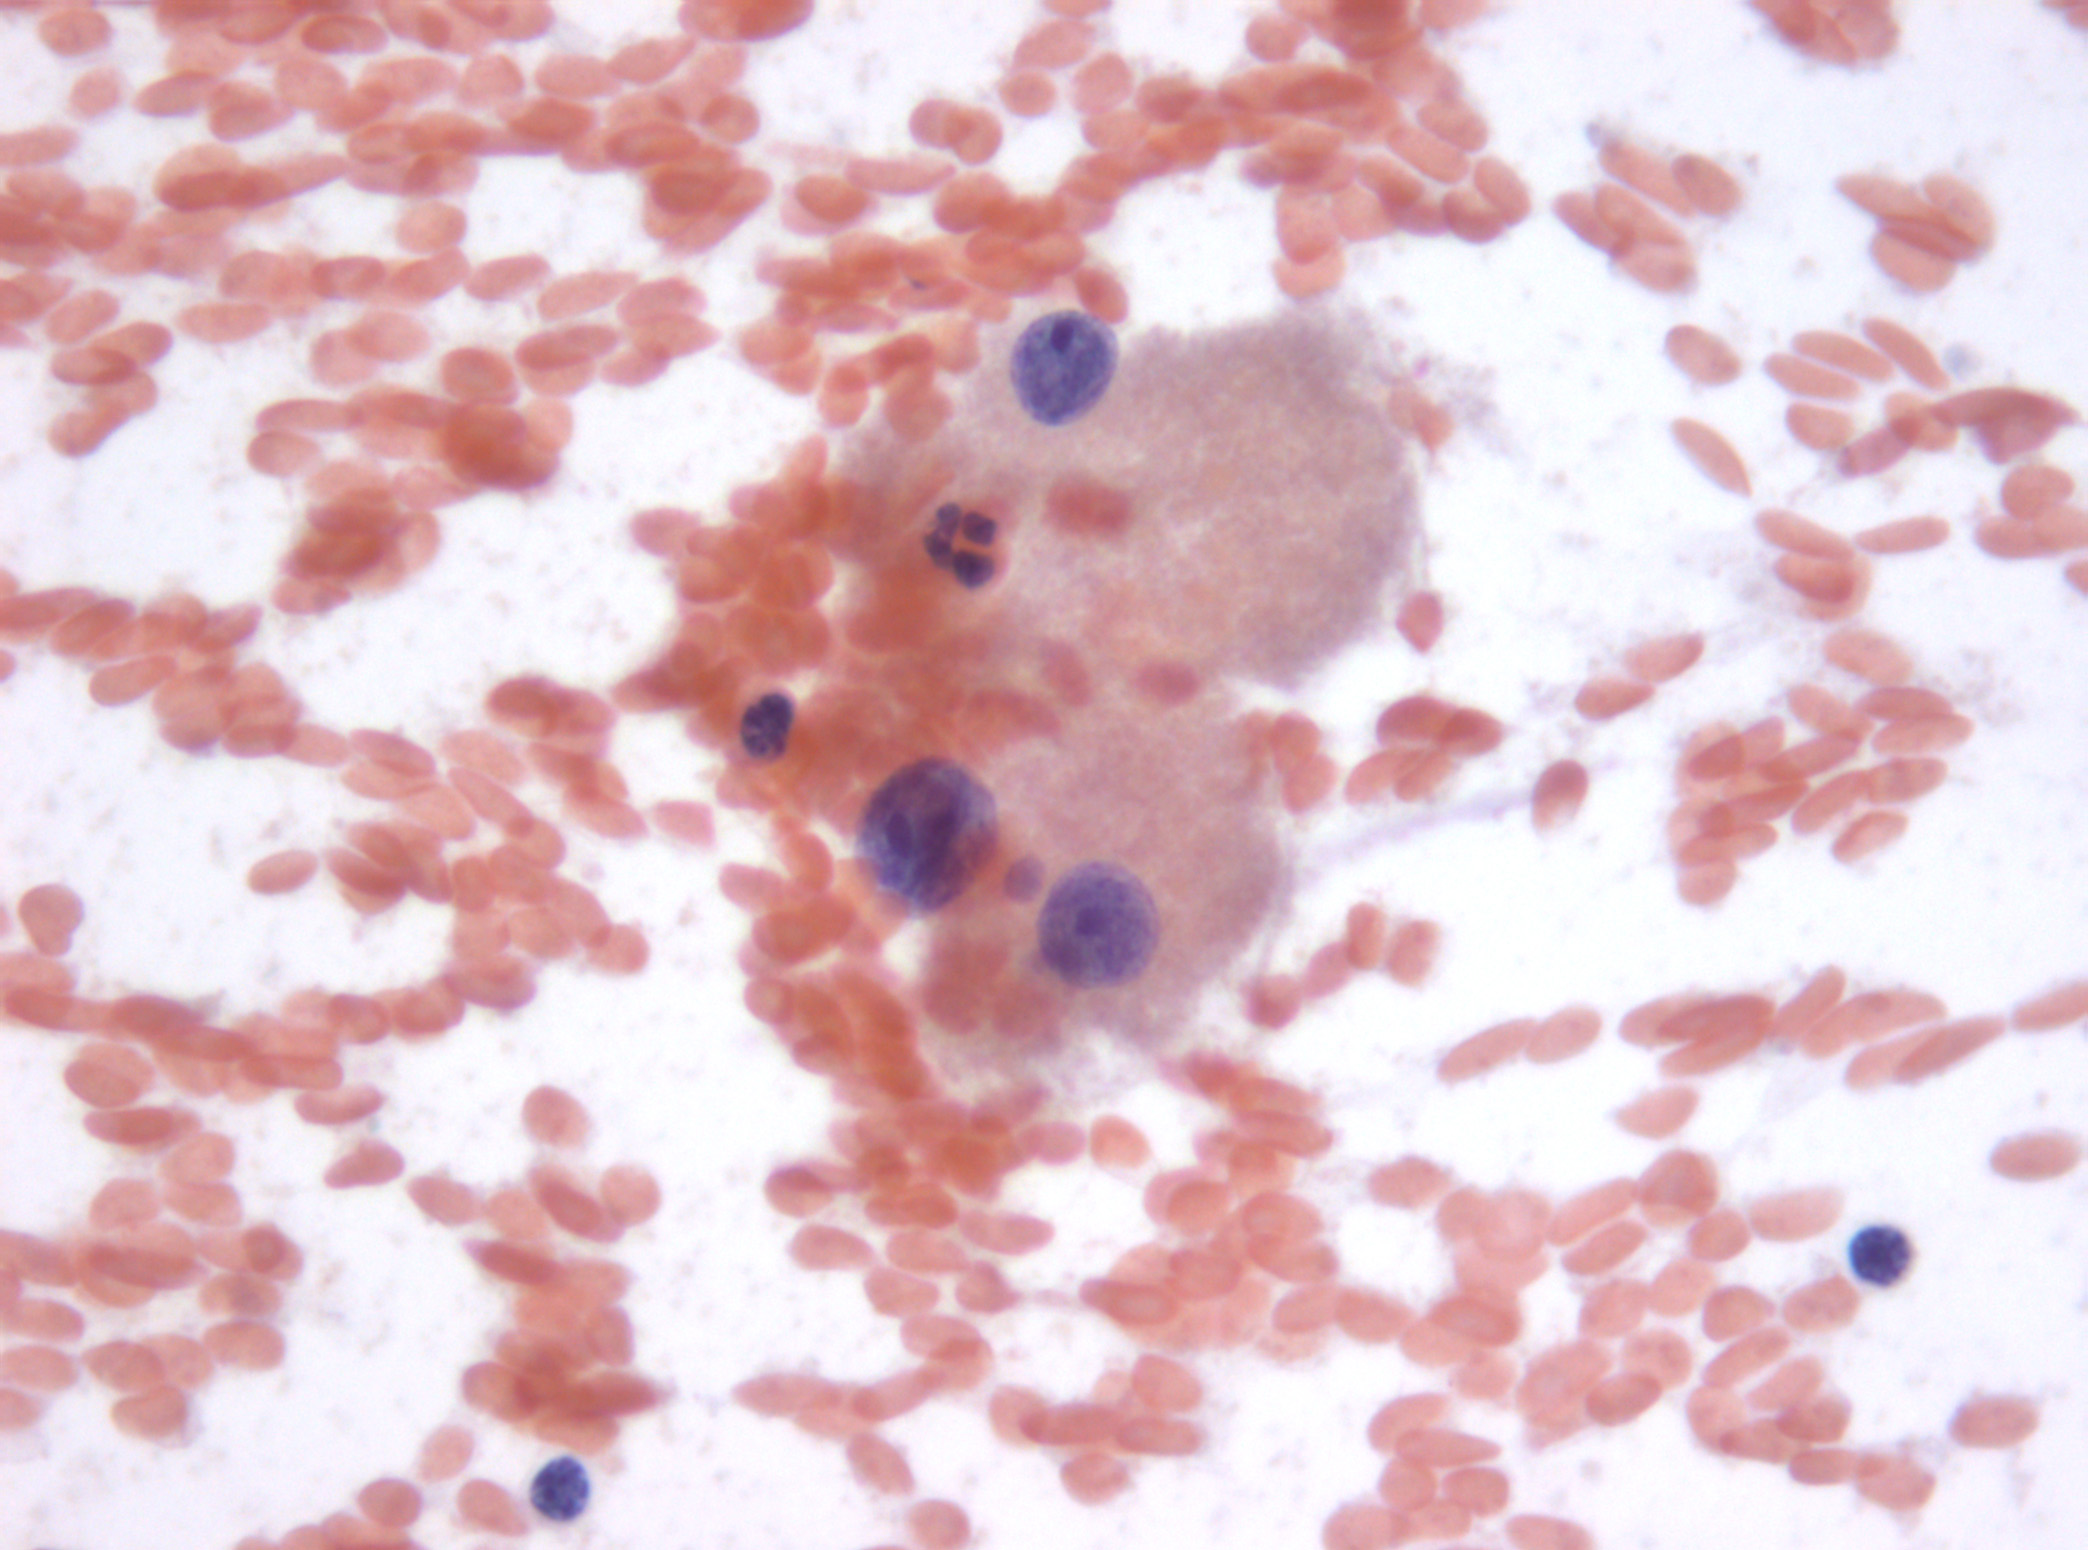

Dra. Mª Rosa Bella (patòleg) i Dr. Mario Prenafeta (radiòleg).

Hospital Universitari Parc Tauli Sabadell

Dona de 59 anys, fumadora de 15-20 cigarretes/dia fins fa 10 anys, sense altres hàbits tòxics destacables, amb antecedents patològics de Diabetes Mellitus tipus I que tracta amb insulina, Hipertensió arterial, i dislipèmia. Consulta per cuadre progressiu desde fa 5-6 mesos d'anosmia, cefalees hemicraneals esquerres, hipoestesia d'hemicara esquerra, epistaxis esquerres que es fan diàries, visió borrosa amb diplòpia, i tumefacció cervical esquerra. A l'exploració física s'observa exoftalmos esquerre i adenopaties laterocervicals esquerres indurades, i a l'estudi ORL s'observa lesió polipoidea eritematosa a fossa nasal provinent de meat superior esquerre. Es realitzen diverses proves de Diagnòstic per la imatge, i es realitzen simultàniament punció aspirativa i biòpsia de la lesió a fossa nasal. S'adjunten imatges de la RNM cranial, i de punció aspirativa.